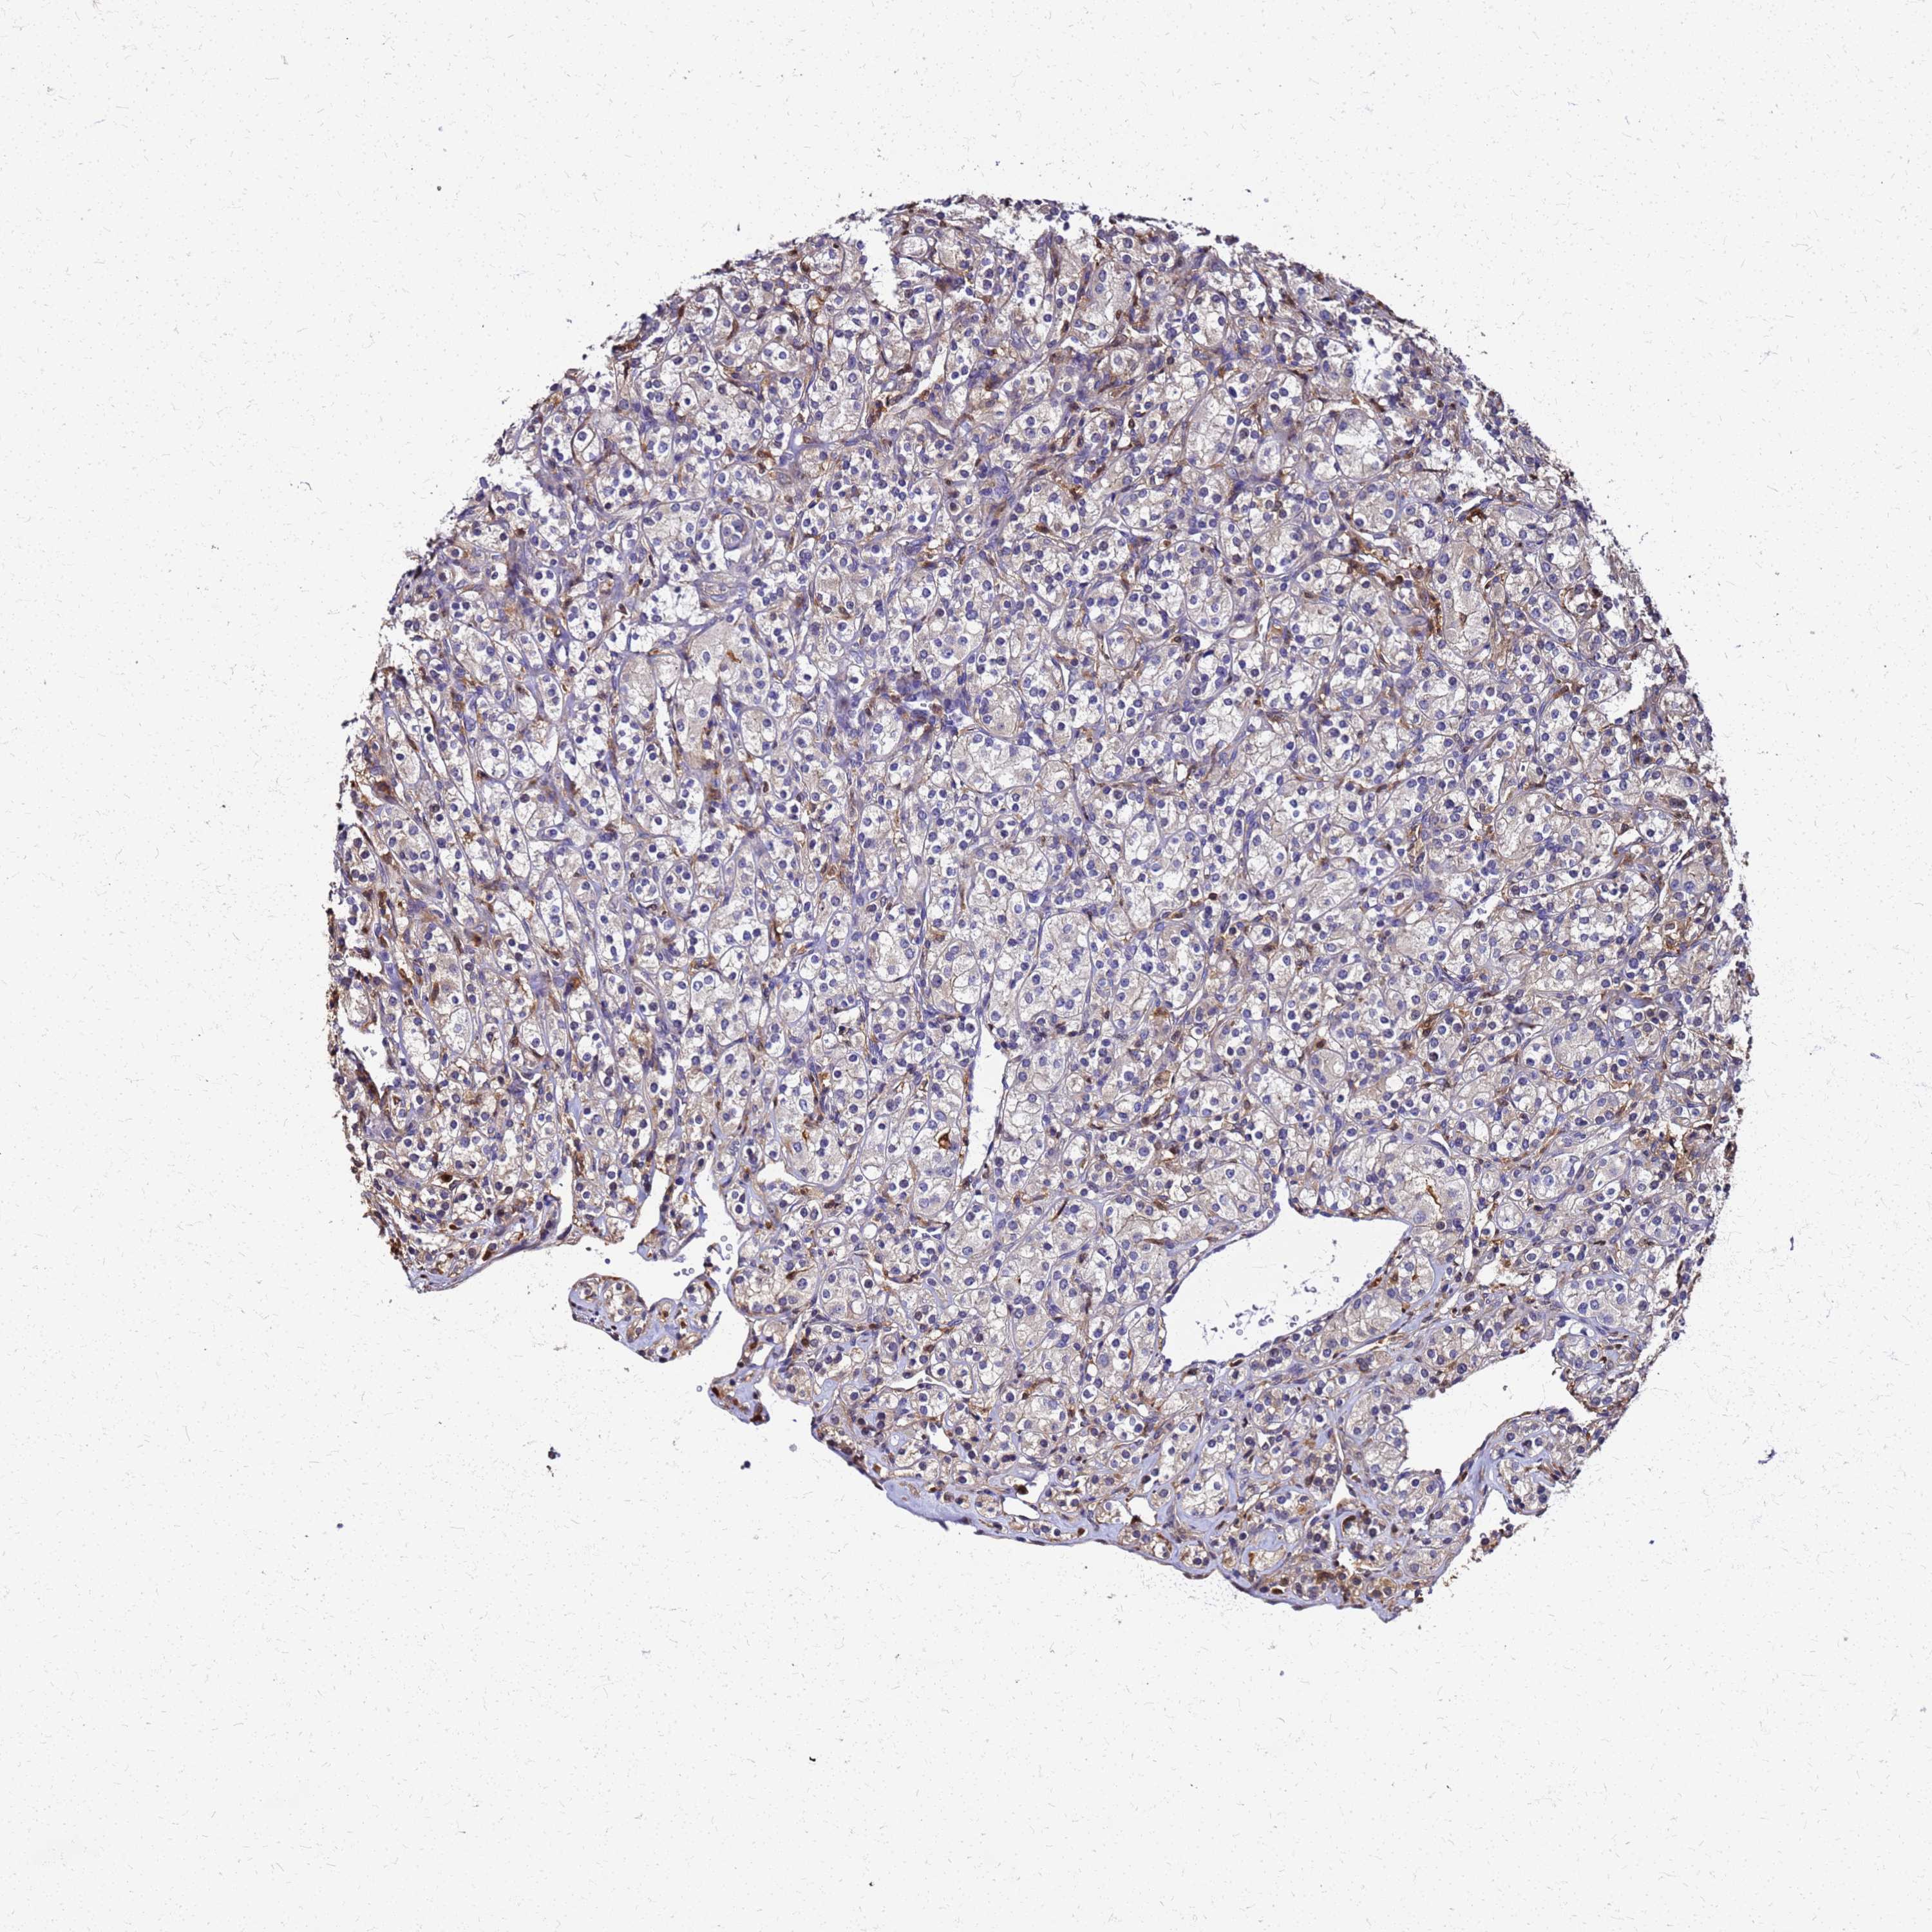

S100A11 is validated prognostic, high expression is unfavorable in Kidney Renal Clear Cell Carcinoma (TCGA)

Best expression cut offi

Based on the FPKM value of each gene, patients were classified into two groups and association between prognosis (survival) and gene expression (FPKM) was examined. The best expression cut-off refers the FPKM value that yields maximal difference with regard to survival between the two groups at the lowest log-rank P-value. Best expression cut-off was selected based on survival analysis .

When clicking on this number, the vertical dashed line indicating cut-off, the interactive survival plot, and the Kaplan-Meier curve will be adjusted to show results based on the best expression cut-off.

: 1146.81

TCGA RNA samplesi

RNA-seq data is reported as average FPKM (number Fragments Per Kilobase of exon per Million reads), generated by the The Cancer Genome Atlas (TCGA) .

Normal distribution across the dataset is visualized with box plots, shown as median and 25th and 75th percentiles. Points are displayed as outliers if they are above or below 1.5 times the interquartile range. FPKM values of the individual samples are presented next to the box plot.

Average pTPM 983.0

Number of samples 521